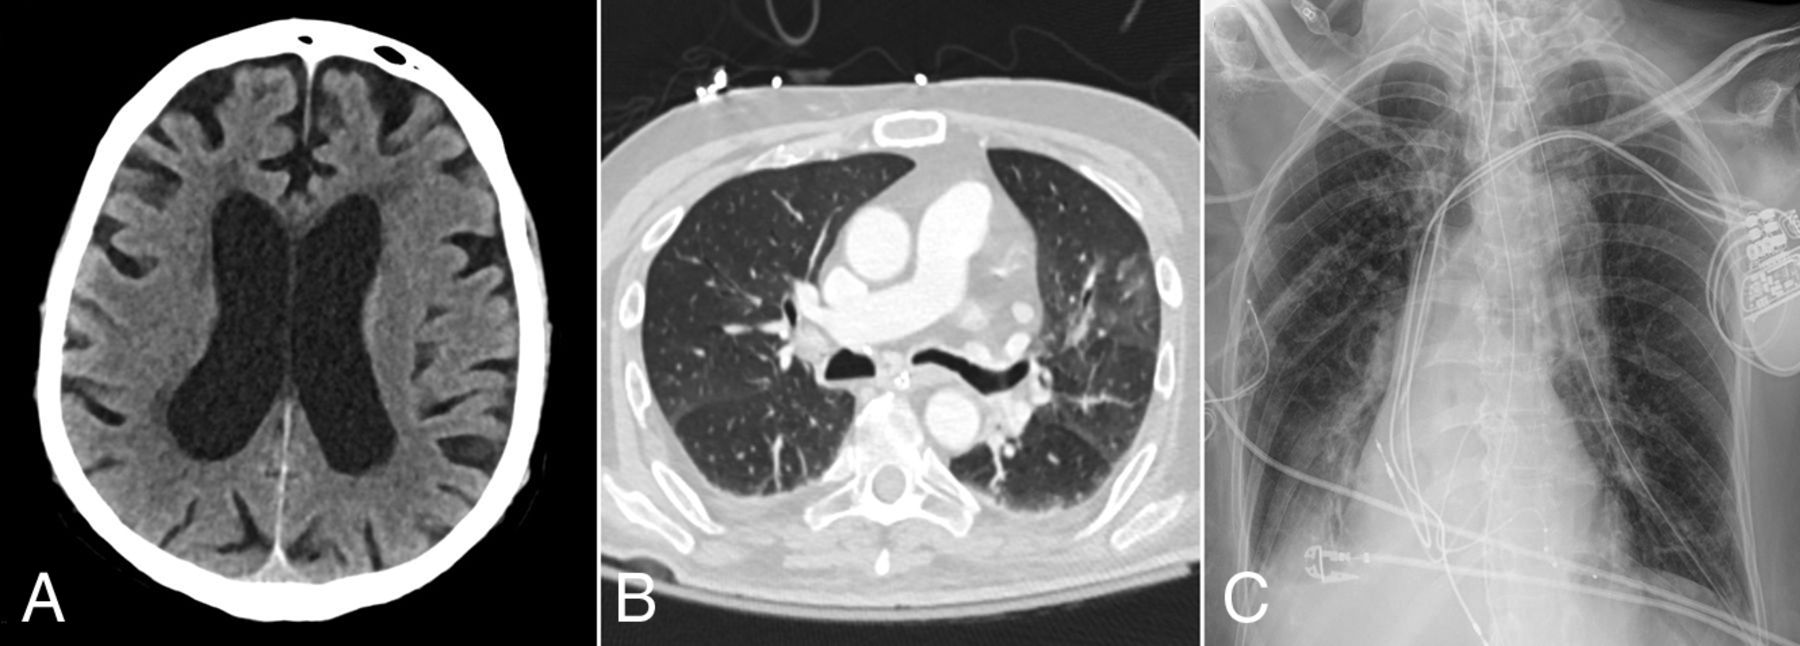

Of the 24 patients with acute neuroimaging findings, 7 patients were found to have intracranial hemorrhage (Fig 1), 7 patients were found to have acute infarction (Fig 2), 6 patients were found to have leukoencephalopathy (Fig 3), 3 patients had intracranial hemorrhage and infarction, and 1 patient had intracranial hemorrhage, infarction, and leukoencephalopathy (Table 2). Sixty-nine patients did not have acute neuroimaging findings (Fig 4). There was no significant difference (P = .225) between the distribution of Radiological Society of North America categories of chest CT findings between patients without acute neuroimaging findings (n = 66) and those with acute neuroimaging findings (n = 14), with the “typical” category being the most prevalent in both groups (Table 2).21

A 67-year-old woman presented with hypoxemic respiratory failure. Axial non-contrast-enhanced head CT image (A) shows no acute findings. B, Chest CT image of the patient demonstrates bilateral peripherally distributed ground-glass opacities involving 4 of the 5 lobes with a CCS score of 8. D, Portable chest radiograph demonstrates bibasilar patchy opacities with a PXS score of 4.4.